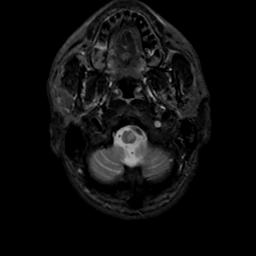

MR Study #7, March 24, 1991 -- Slice #3

[Home][Help][Clinical][Tour 1][Tour 2] Slice 3